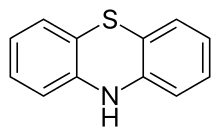

| Phenothiazine |  Phenothiazine |